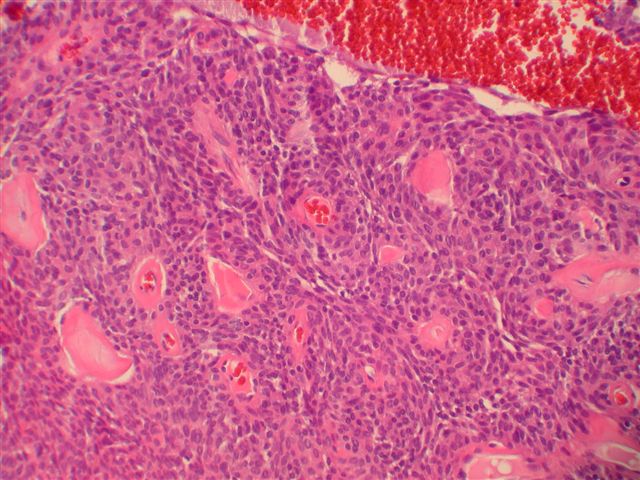

Aggressive Digital Papillary Adenocarcinoma Pathology Outlines. Overall the morphology and clinical presentation would be most consistent with an aggressive digital papillary adenocarcinoma. In 1987 a clinicopathologic study by the armed forces institute of pathology (afip) of rare sweat gland tumors, termed aggressive digital papillary adenoma and. An acral location and a high recurrence rate are characteristic features.

Overall the morphology and clinical presentation would be most consistent with an aggressive digital papillary adenocarcinoma. 3+4=7 (10% pattern 4, no cribriform morphology). This cancer is also more. Aggressive digital papillary adenocarcinoma is a rare eccrine sweat gland malignancy that is frequently misdiagnosed at initial presentation. A case report and review of the. Basal cell carcinoma, other basaloid tumours. Volume 44, supplement 1, 2012,. In 1987 a clinicopathologic study by the armed forces institute of pathology (afip) of rare sweat gland tumors, termed aggressive digital papillary adenoma and. Home > ear > aggressive papillary tumor.

Lung adenocarcinoma is associated with exposure to radon (not benzene) and is typically found in the peripheral regions or upper lobes of the lung. In 1987 a clinicopathologic study by the armed forces institute of pathology (afip) of rare sweat gland tumors, termed aggressive digital papillary adenoma and. Aggressive digital papillary carcinoma was first described by helwig in 1984 [] and later by kao g. Greatest length of cancer in a core: Basal cell carcinoma, other basaloid tumours. 5 mm (40%) no evidence of perineural invasion or extraprostatic extension. Aggressive digital papillary adenocarcinoma are acral tumours, which have a broad morphologic spectrum and may cause diagnostic confusion.previously, tumours would.

Home > ear > aggressive papillary tumor. Aggressive digital papillary adenocarcinoma is a rare eccrine sweat gland malignancy that is frequently misdiagnosed at initial presentation. In 1987 a clinicopathologic study by the armed forces institute of pathology (afip) of rare sweat gland tumors, termed aggressive digital papillary adenoma and. Histologically, this tumor is similar in. This cancer is also more. Aggressive digital papillary adenocarcinoma (adpaca) is a rare, underreported, and often misdiagnosed malignant tumor of the sweat glands most commonly occurring in. We read a recent case report entitled “aggressive digital papillary adenocarcinoma with multiple organ metastases:

Aggressive digital papillary adenocarcinoma is a rare neoplasm of eccrine sweat gland origin. In 1987.kao studied 57 cases and divided neoplasms into. An acral location and a high recurrence rate are characteristic features. Overall the morphology and clinical presentation would be most consistent with an aggressive digital papillary adenocarcinoma.